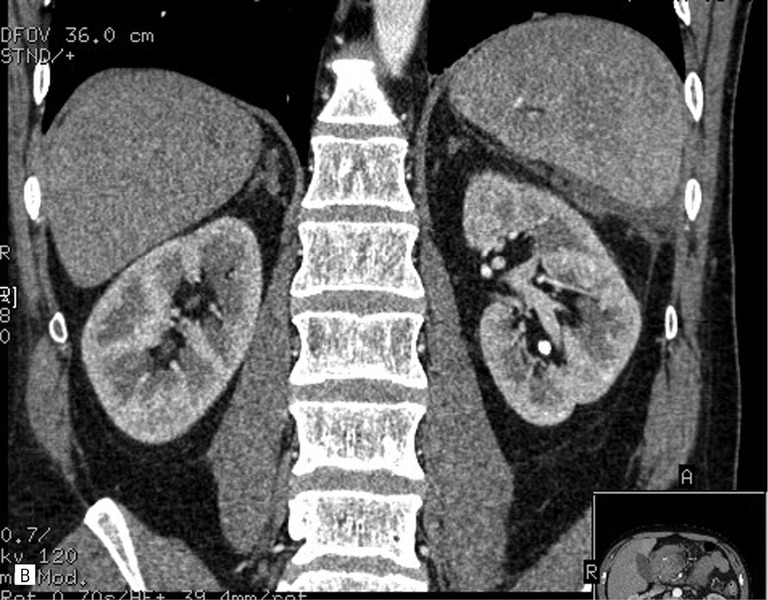

55-letni mężczyzna został przyjęty na oddział chirurgiczny z powodu silnych bólów brzucha, wymiotów i zaburzeń oddawania stolca – objawów sugerujących ostre zapalenie trzustki. W badaniach laboratoryjnych potwierdzono rozpoznanie. Wykonano badanie USG, które ujawniło powiększenie trzustki i zatarcie jej echostruktury. Pełną ocenę utrudniało napięcie powłok brzusznych, obrzęk krezki oraz obecność gazu w rozdętych pętlach jelit. Wykonano dwufazowe badanie TK, które potwierdziło obecność obrzękowej postaci zapalenia trzustki. Nie stwierdzono wówczas płynu w jamie otrzewnej. Śladowa ilość płynu była widoczna w lewej jamie opłucnowej (ryc. 1).

Rycina 1. Badanie TK w ostrej fazie zapalenia trzustki. A. Przekrój poprzeczny. Widoczne znaczne poszerzenie trzustki (obrzęk) z obecnością nacieku zapalnego w otaczającej tkance tłuszczowej, penetrującego wzdłuż naczyń w kierunku widocznej fragmentarycznie (biegun przedni) śledziony. B. Przekrój czołowy. Widoczna niepowiększona śledziona. Cechy nacieku zapalnego w okolicy przedniego bieguna. Bez cech nacieku i przestrzeni płynowych w otoczeniu nerek i mięśni biodrowo-lędźwiowych.